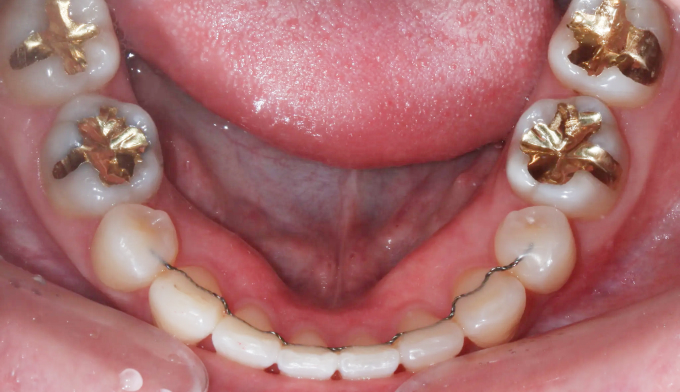

전에 교정치료를 마무리하고 지내던 중 치아 안쪽에 붙여놓은 유지장치가 떨어지면서 관리를 못하게 된 경우입니다. 이런 경우 앞니가 다시 틀어지거나 벌어질 수 있습니다.

위 유지장치는 모두 제거되어보이고, 아래 유지장치 또한 양 끝이 끊어져서 치아사이가 벌어져 보입니다.

서비스직에서 일하고 있어 치아 안쪽으로 붙이는 설측교정을 원하였고, 9개월만에 교정치료 종료 하였습니다.

유지장치가 떨어지면서 벌어진 치아들과 깊어진 앞니들을 이상적인 위치로 배열시켰습니다.